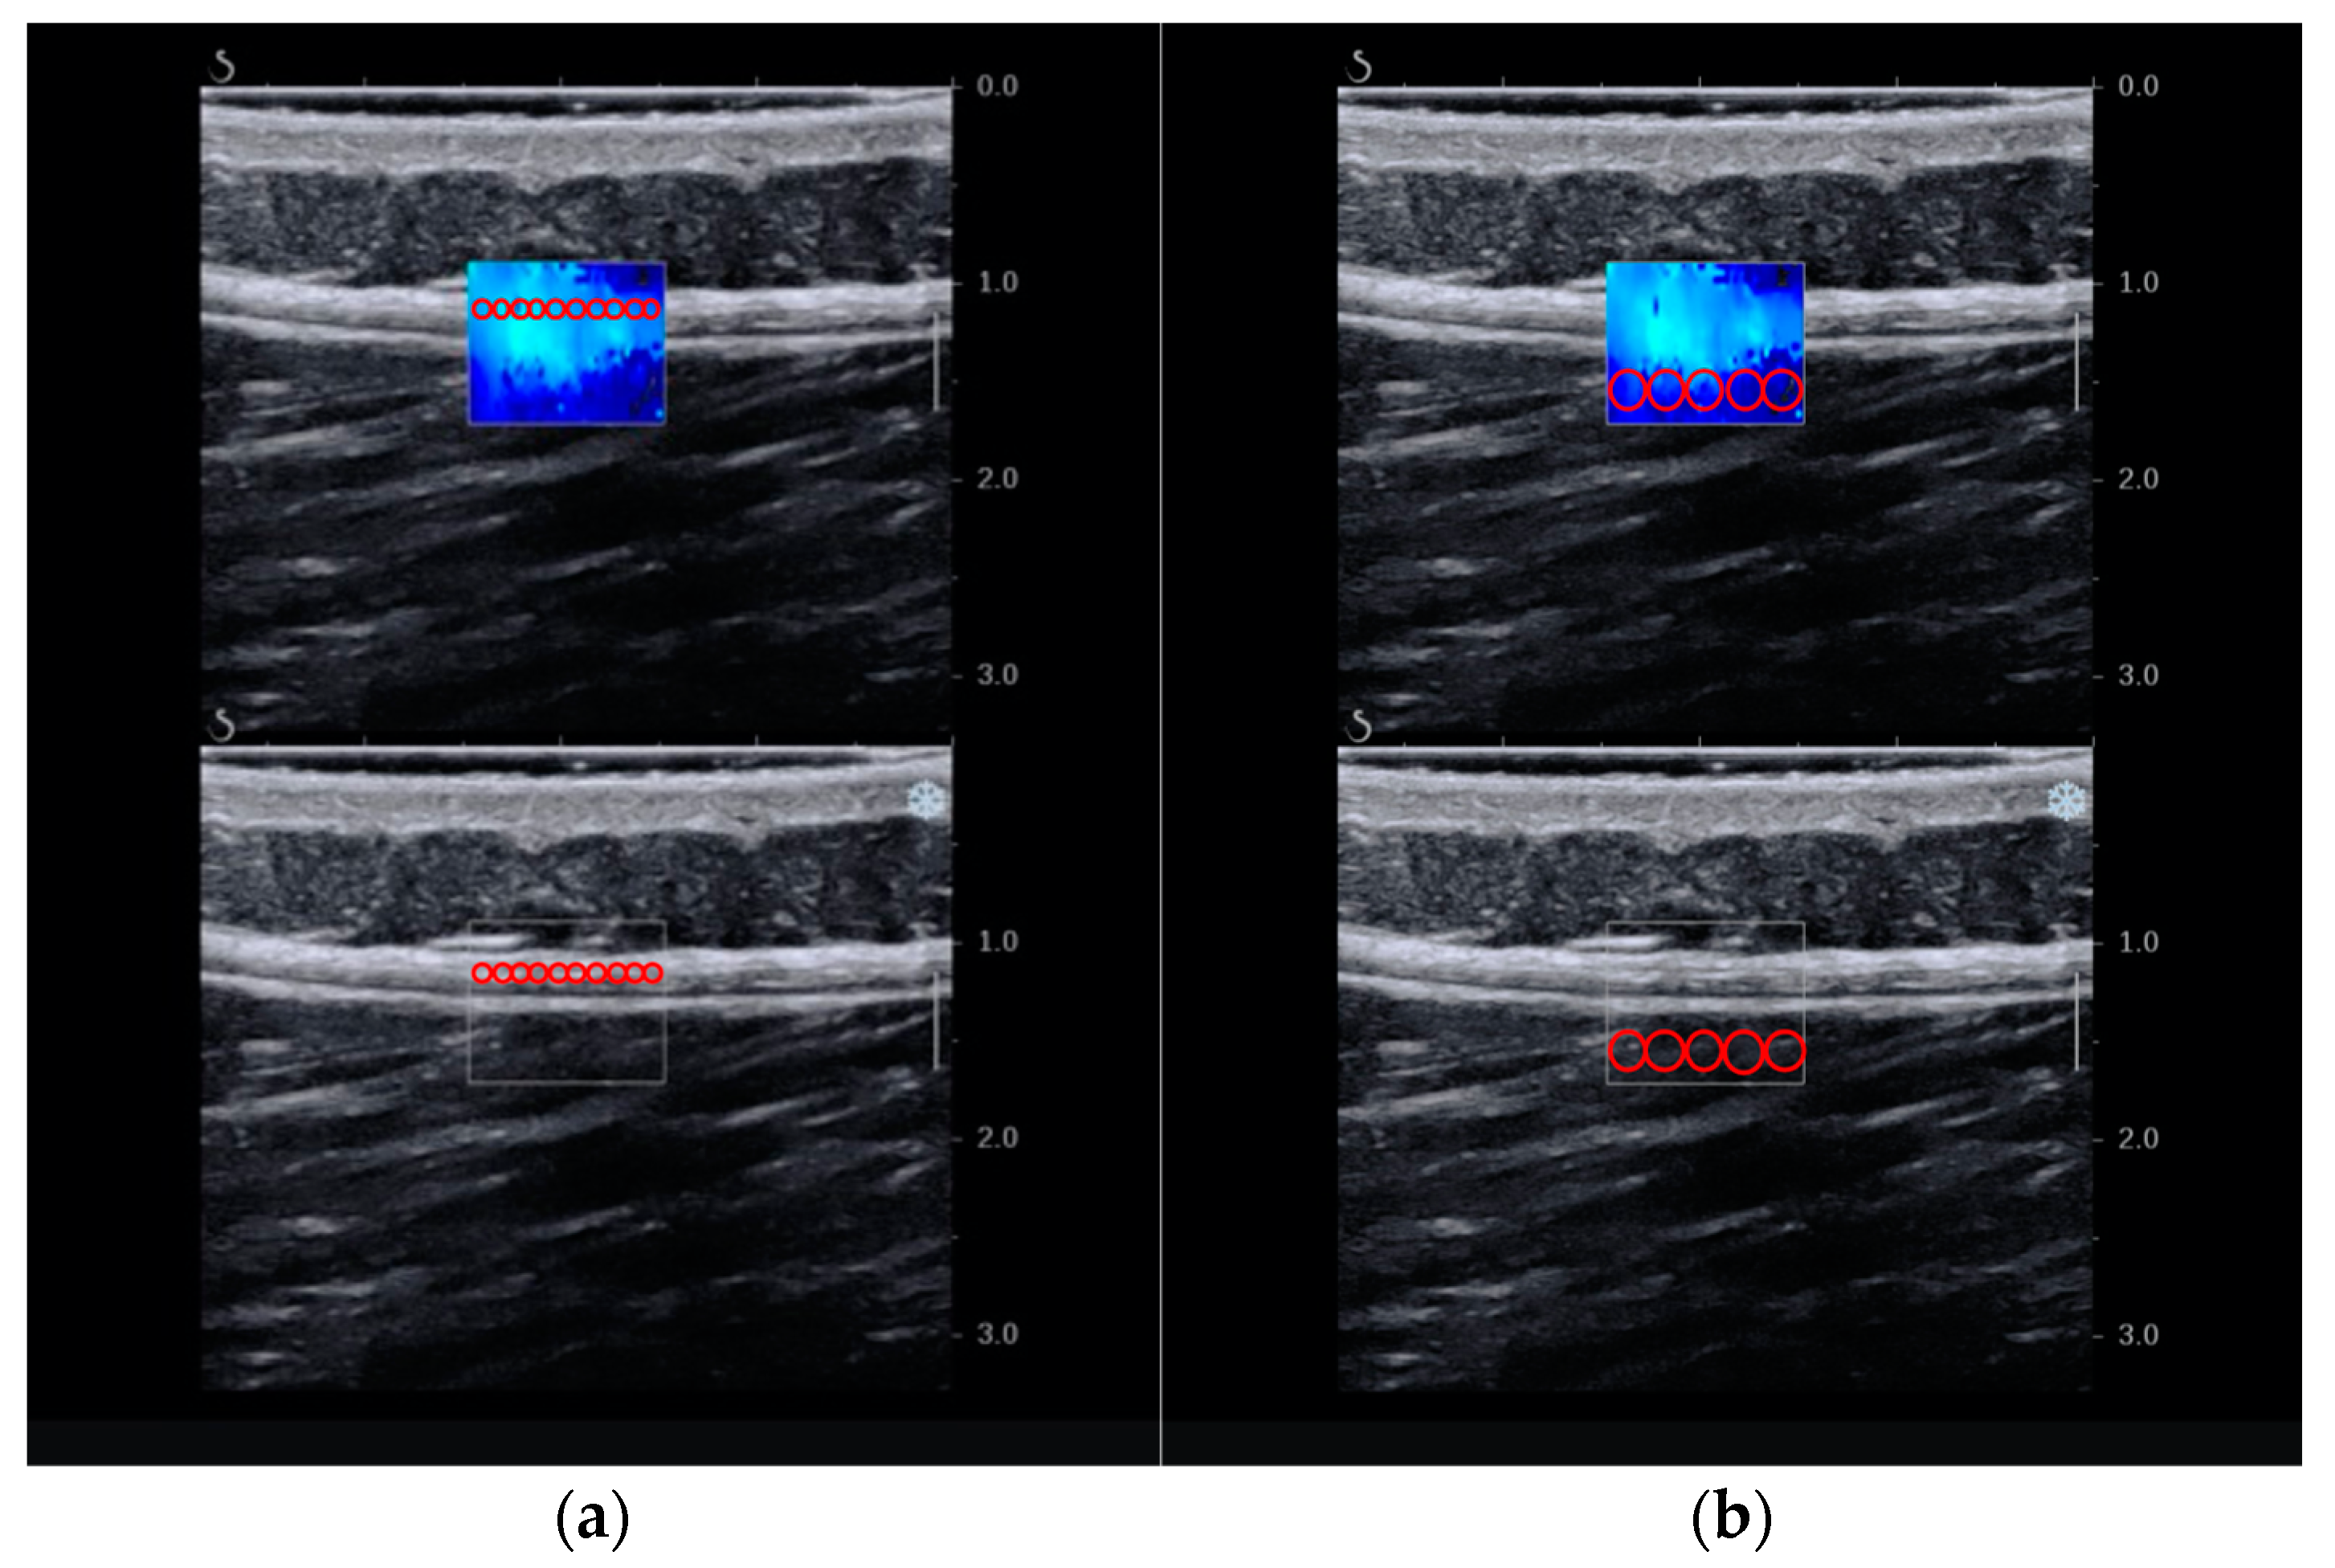

2.6.1. Primary Outcome—Stiffness

2.6.2. Secondary Outcome—Thickness